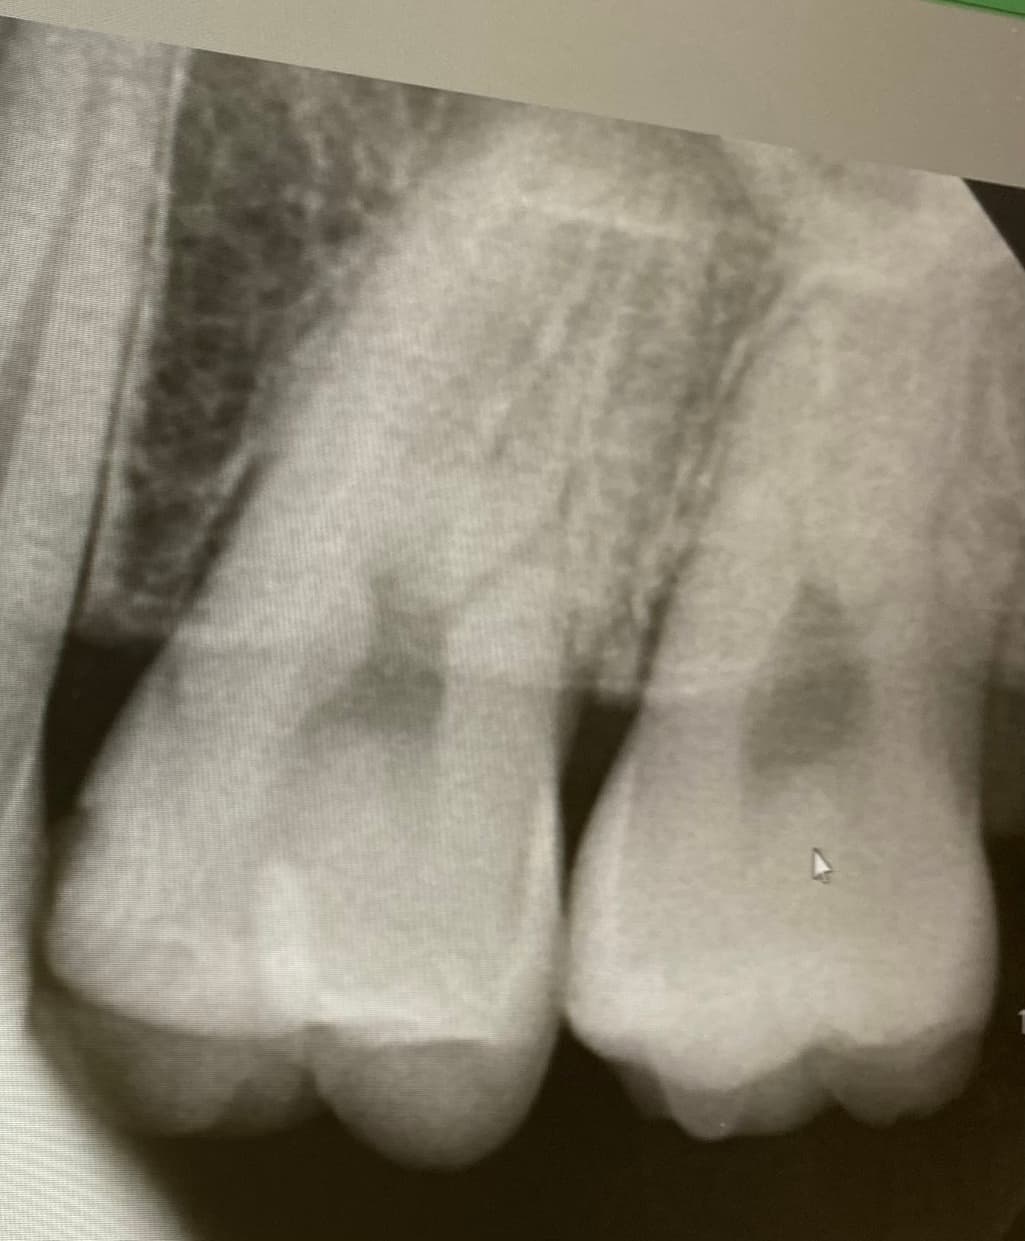

왼쪽 위 2번째 어금니 레진속 2차 충치로

육안으로 봤을 경우에는 인접면에 충치가 있는 것으로 보이긴 합니다. 하지만 엑스레이 사진상으로 크게 보이지 않기 때문에 관리를 해서 사용할 수 있는 경우도 있습니다. 충치가 더 커지는 것을 방지하기 위해 예방적으로 치료를 하고자 한다면 치료가 필요할 수 있으며 그렇지 않다면 관리를 하면서 상태를 지켜볼 수 있습니다.

치료여부는 평상시 관리상태나 구강상태에 따라 갈릴 수 있으며 지아이는 거의 쓰지 않습니다.